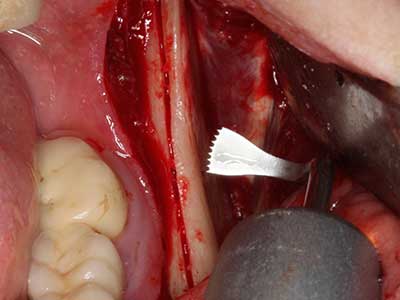

Пиезохирургията има допълнителни предимства при събиране на костни блокове. В допълнение към високата прецизност при остеотомията, описана по-горе, употребата на фините режещи накрайници значително намаляват загубата на материал. Голяма загуба на материал по време на събиране може да се очаква с дебелите накрайници, особено при употреба на борери Линдеман (Lakshmiganthan, Gokulanathan et al. 2012). Базалното разделяне, което е необходимо, особено за присадка на блок при ретромолар, е улеснено от специално създадени правоъгълни триони. В резултат на това, пиезохирургията е разглеждана като прецизна, улеснена и безопасна процедура за събиране на костни блокове в ретромоларното пространство (Happe 2007) (Фиг. 1-12).

Когато се извършват хирургични процедури върху кост в непосредствена близост до чувствителни структури като кръвоносни съдове или нерви, ротиращите инструменти създават значителен риск за ятрогенно нараняване. Пиезоелектрическите апарати могат да бъдат от помощ при препарация на костно покритие и отстраняване на твърда кост близо до нерви, особено за оголване на нервите след ятрогенно нараняване, както и по време на латерализация на нервите за резекционни и реконструктивни процедури или поставяне на имплант (Фиг. 17-20). Лекият контакт между пиезонакрайника и нерва по принцип не води до нараняване, но ако действате непредпазливо с трионообразни движения или приставки за остатъчен костен субстрат, може да причините временно или перманентно увреждане на нерва. Въпреки това, рискът от увреждане се счита за много по-малък, отколкото при употреба на триони или ротиращи инструменти (Pereira, Gealh et al. 2014).